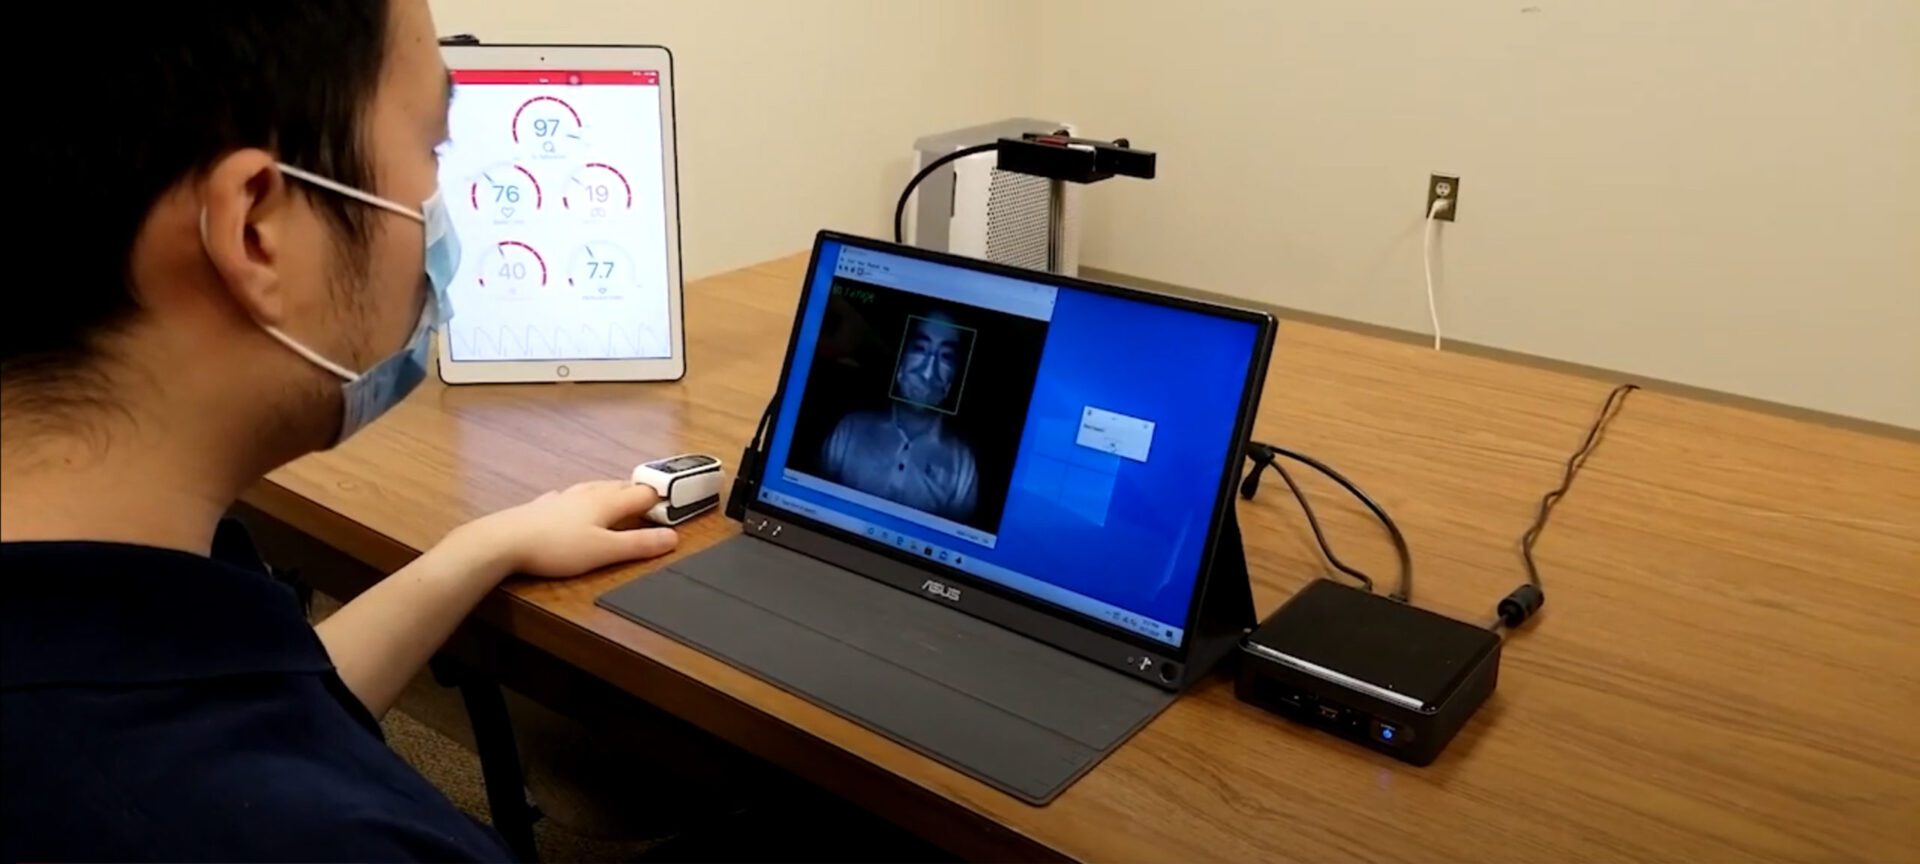

Touchless respiratory and heart rate measurement for COVID-19 health screening

New technology provides a contactless method to add respiratory rate and heart rate to temperature readings .

Turning faces into thermostats

An autonomous HVAC system could provide more comfort with less energy.

The post Turning faces into thermostats appeared first on Michigan Engineering News.